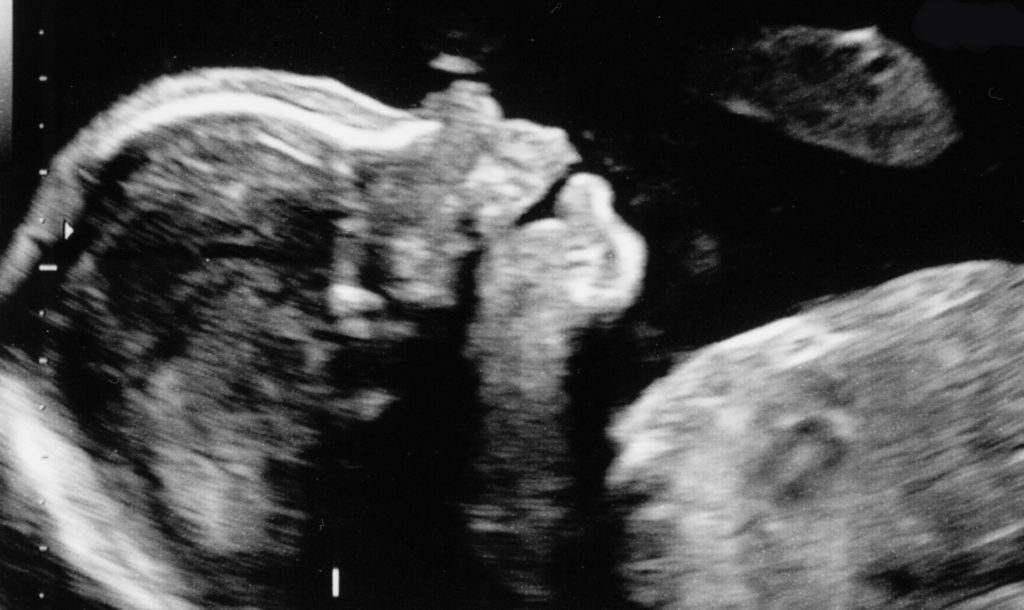

At 20 weeks, we had our “big” ultrasound. Because of my age, we went to a high-risk ob. The ultrasound showed a beautiful, mostly healthy baby boy. There were a couple concerns that warranted a follow-up ultrasound eight weeks later. We weren’t overly worried because it seemed everything was just on the outer edge of normal. Eight weeks later I reported for my follow-up. This time, his stomach was bigger than normal and warranted a diagnosis. We are still hopeful that his condition might resolve before he is born. Also, after researching, we have learned that while it does require surgery to correct most times, it is a surgery with few complications and a high success rate. We have learned that many times it is a condition that is not discovered until the baby or even child is in a medical crisis. We are blessed to know now in order to prepare and be vigilant. However, instead of being thankful, I started blaming myself. “If only I had done this…” or “if only I had NOT done that…” Somehow in my mind, this diagnosis was my fault (even though many studies show that they don’t know what causes it). Have you ever done that?